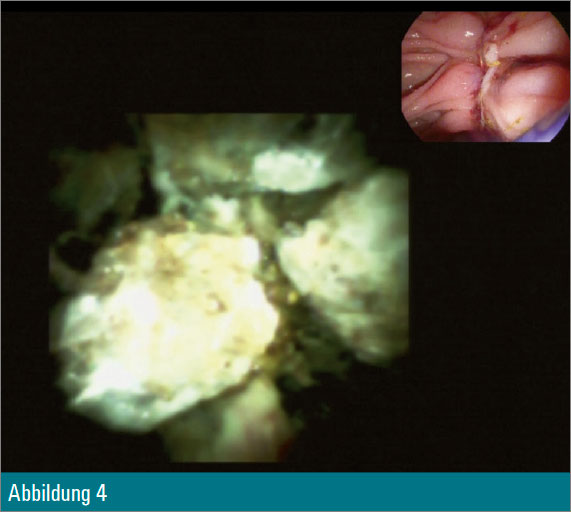

Trotz Fragmentierung des Konkrements (Abbildung 4) waren mehrfache mechanische Lithotripsien mit dem Dormiakörbchen in derselben Sitzung notwendig. Schlussendlich konnten alle Fragmente erfolgreich mit dem Ballon geborgen werden (Abbildung 5).